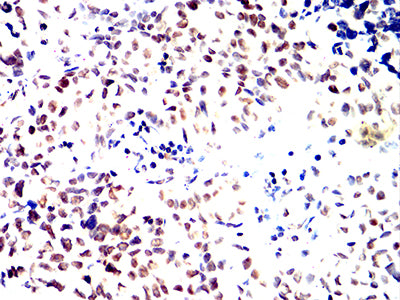

- Immunohistochemical analysis of paraffin-embedded human bladder cancer tissues using RFA2 mouse mAb with DAB staining.